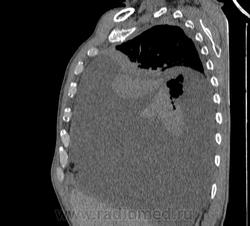

Пожилой мужчина, лечился по н/д правостороннней пневмонии в терап/отделении. Жалобы на одышку, кашель. По результатам Р-контроля после лечения направлен на КТ легких с диагнозом: плеврит справа, распад? В корне правого легкого вижу объёмное образование, с распадом. Смущают размеры плеврита,очень много жидкости, почти до 3 ребра. Анализы крови спокойные- L4,0-6,6, СОЭ 12-16мм. Неужто ТБС, отсев бы был при таком огромном поражении. В посеве мокроты-100% высев клебсиэллы пневмоние. Мокрота на общий анализ в работе-собирает с трудом, изза отсутствия мокроты. Плевральную пункцию еще не проводили. Н азначила бронхоскопию и плеврал пункцию. Как думаете, уважаемые коллеги, это онкопроцесс или тбс распад?

Самое интересное забыла показать- может это 100% навеет на мысль об опухолевом процессе, остеолитическая деструкция позвонка?

Не смотря дайкомы, только по рентгенограмме, предположил бы центральный рак правого легкого. Потому что большой гидроторакс, без смещения средостения в здоровую сторону, как правило, соответствует раковому ателектазу.

Коллеги, распада там нет, это вас медиастинальное окно подвело. В грудине тоже все в порядке. Да и компрессия позвонка "старая".

Небольшое количество увеличенных лимфоузлов, и те - не сказать, чтоб были очень крупными. От эмпиемы до онкологии... Умеренное количество жидкости в перикарде, толщиной слоя до 13-14 мм. При подобной картине не вижу смысла гадать по сжатому лёгкому, пишу так: массивный выпот справа, около 2500 мл, диафрагма оттеснена жидкостью каудально, печень (!!!) смещена каудально и вправо. Легкое справа значительно компрессировано жидкостью, оценка проходимости бронхов и состояния легочной паренхимы (кроме имеющейся эмфиземы) практически невозможна. Необходима пункция плевральной полости справа (цитология, ВК, посев на микрофлору и проч), КТ-контроль после эвакуации жидкости.